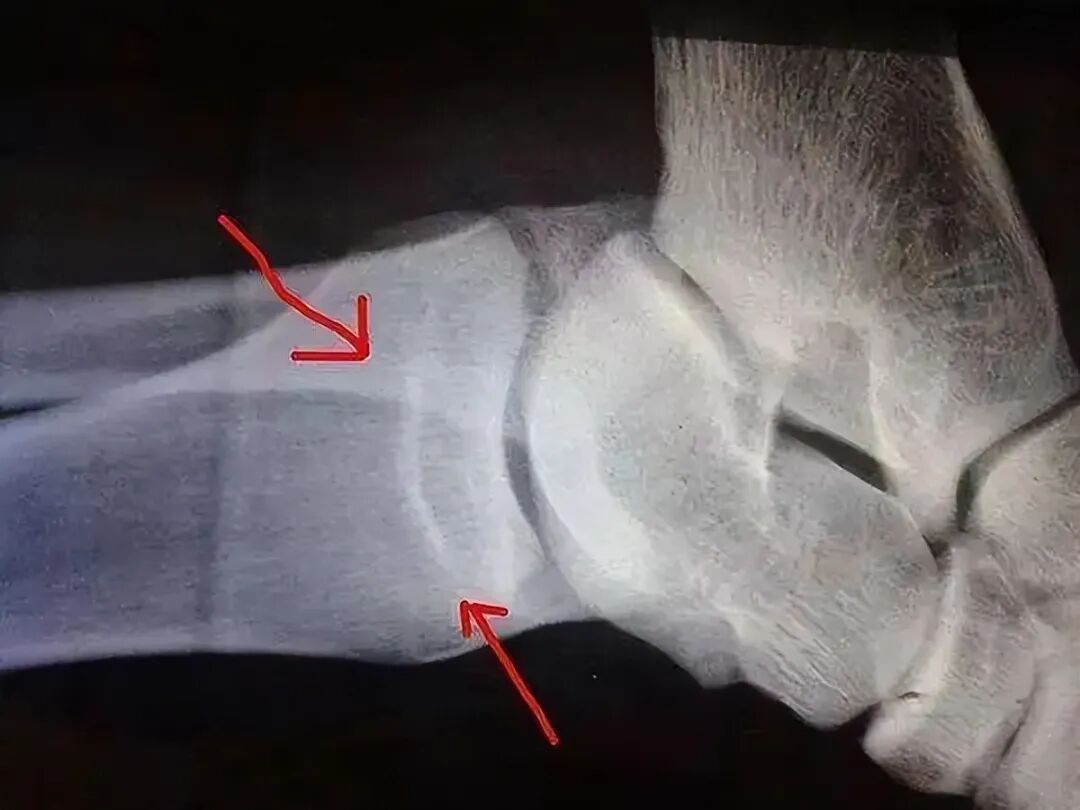

有很多医生都说过,孩子骨骼线一旦完全闭合,就代表骨骼的生长发育已经完成,孩子的身高基本就定型了。所以,要趁孩子骨骼线闭合前,发育到理想身高。

但是呢,骨骼线我们是无法靠眼睛自测的,为了不让孩子错过最后的长高机会,父母要注意观察孩子的身体特征,以此来判断骨骼线是否快要闭合。